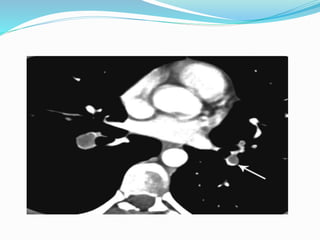

Computed Tomography Angiography

CT pulmonary angiography (i.e., CTA) has become a

favored study for the evaluation of PE.

CTA provides a number of potential advantages over

other imaging modalities in the diagnosis of PE,

including:

(1) direct visualization of the embolus

(2) the ability to assess for other potential causes for the

patient’s complaints such as pneumonia

(3) imaging algorithms that scan through the pelvis and

lower extremities, as well as the chest, allowing

simultaneous evaluation for PE and for DVT